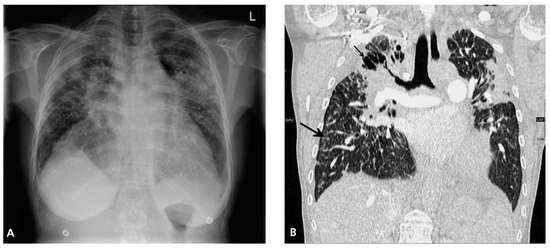

Heart Failure in a Patient with Multi-Organ Sarcoidosis

by Marc Buser, Theresa Dellas Buser, Jens Bremerich and Daniel Tobler

Cardiovasc. Med. 2012, 15(11), 329; https://doi.org/10.4414/cvm.2012.00124 - 21 Nov 2012

A 53-year-old woman was admitted to our emergency department with progressive shortness of breath during exertion for three months. [...] Full article

Figure 1